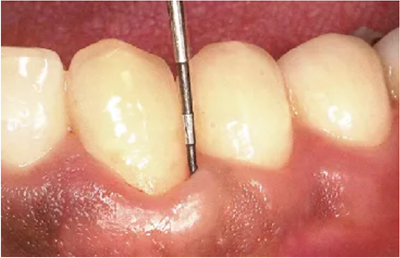

3、鄰接面牙周袋的檢測(cè)

鄰接面是最難以進(jìn)行檢測(cè),測(cè)定結(jié)果也最容易出現(xiàn)誤差的部位。舌側(cè)遠(yuǎn)中等空間狹窄的部位,探針難以插入,而且有牙齒影子的影響,刻度難以讀取。

要充分注意到這些要點(diǎn),并參考X片,盡量做到無漏查。

● 鄰接面正下方的探診

鄰接面的正面檢測(cè)方法。注意大約是在鄰接面部分的中央位置處,將探針略傾斜插入鄰接面的中央點(diǎn)。

檢測(cè)鄰接面正中點(diǎn)下方的牙周袋,探針是無法與牙軸平行插入的。但是緊靠著鄰接點(diǎn)平行于牙軸插入探針,可以檢測(cè)到難以檢測(cè)的鄰接面牙周袋深。

如果從斜側(cè)插入探針檢測(cè)沒有一定的標(biāo)準(zhǔn),那么每次測(cè)出的數(shù)值都會(huì)各不相同,得到的數(shù)據(jù)難以正確分析出問題所在。